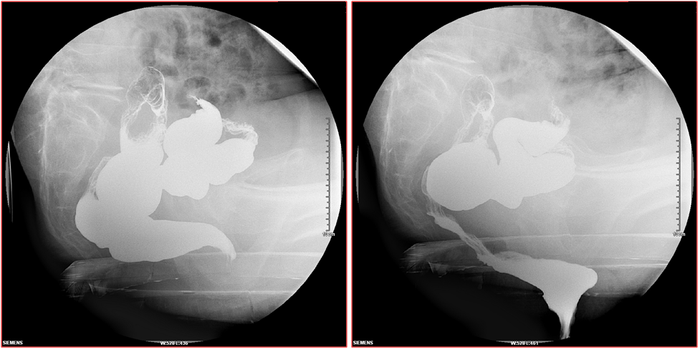

骶神经调节术教程(19)——排粪造影检查 - 微医(挂号网)

图片尺寸700x350